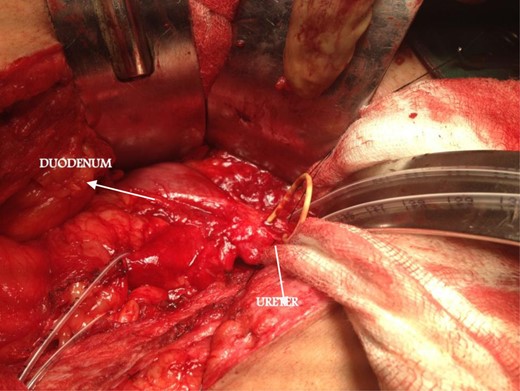

At a later date (1 week later), he underwent exploration in view of ureteroenteric fistula. During surgery, we found a fistulous tract connecting the upper portion of the ureter with the third part of duodenum around 3 cm distal to the pelvis, with upper coil of JJ stent lying into the duodenum (Fig. 2). Fistulous tract was excised, and retained portion of the stent was removed. Duodenum was closed in two layers, and ureterotomy was closed over a new JJ stent. Patient tolerated the procedure well, and the JJ stent was later removed after 2 weeks.